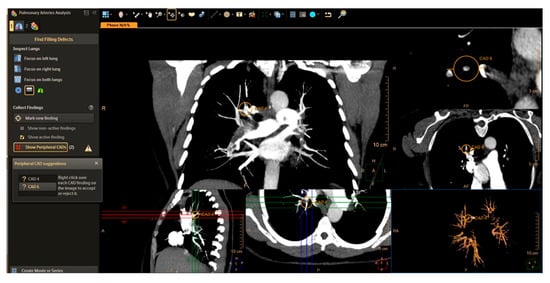

5.1. Computed Tomography Pulmonary Angiography (CTPA)